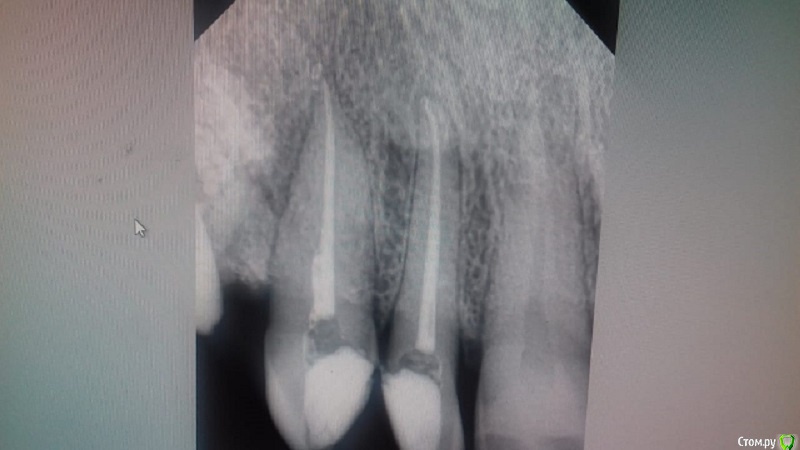

Чаще стали попадаться двухканальные нижние передние зубы или я стал просто чаще находить.

3.3 :

post-52119-0-89230800-1581239363_thumb.jpg